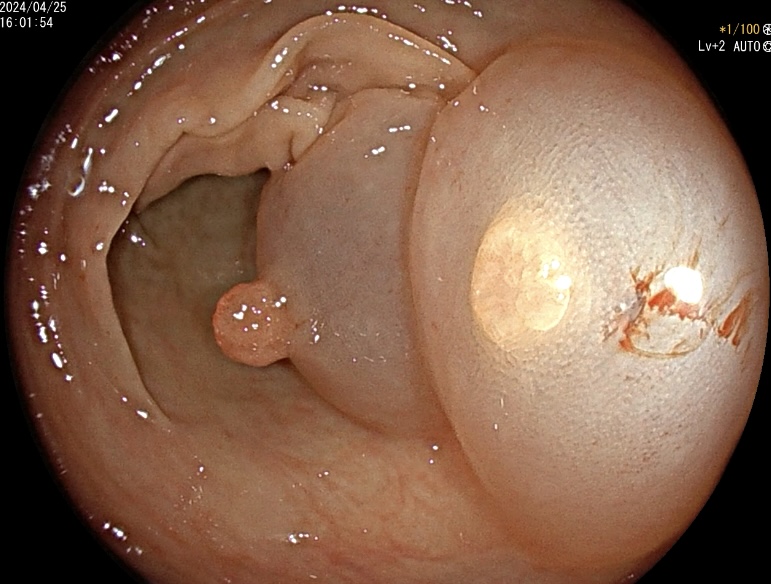

1. 肠道清洁程度对检查结果的影响:清洁良好的肠道能使医生清晰地观察肠道黏膜,发现微小病变。如果肠道准备不充分,残留的粪便会遮挡视线,导致漏诊或误诊。